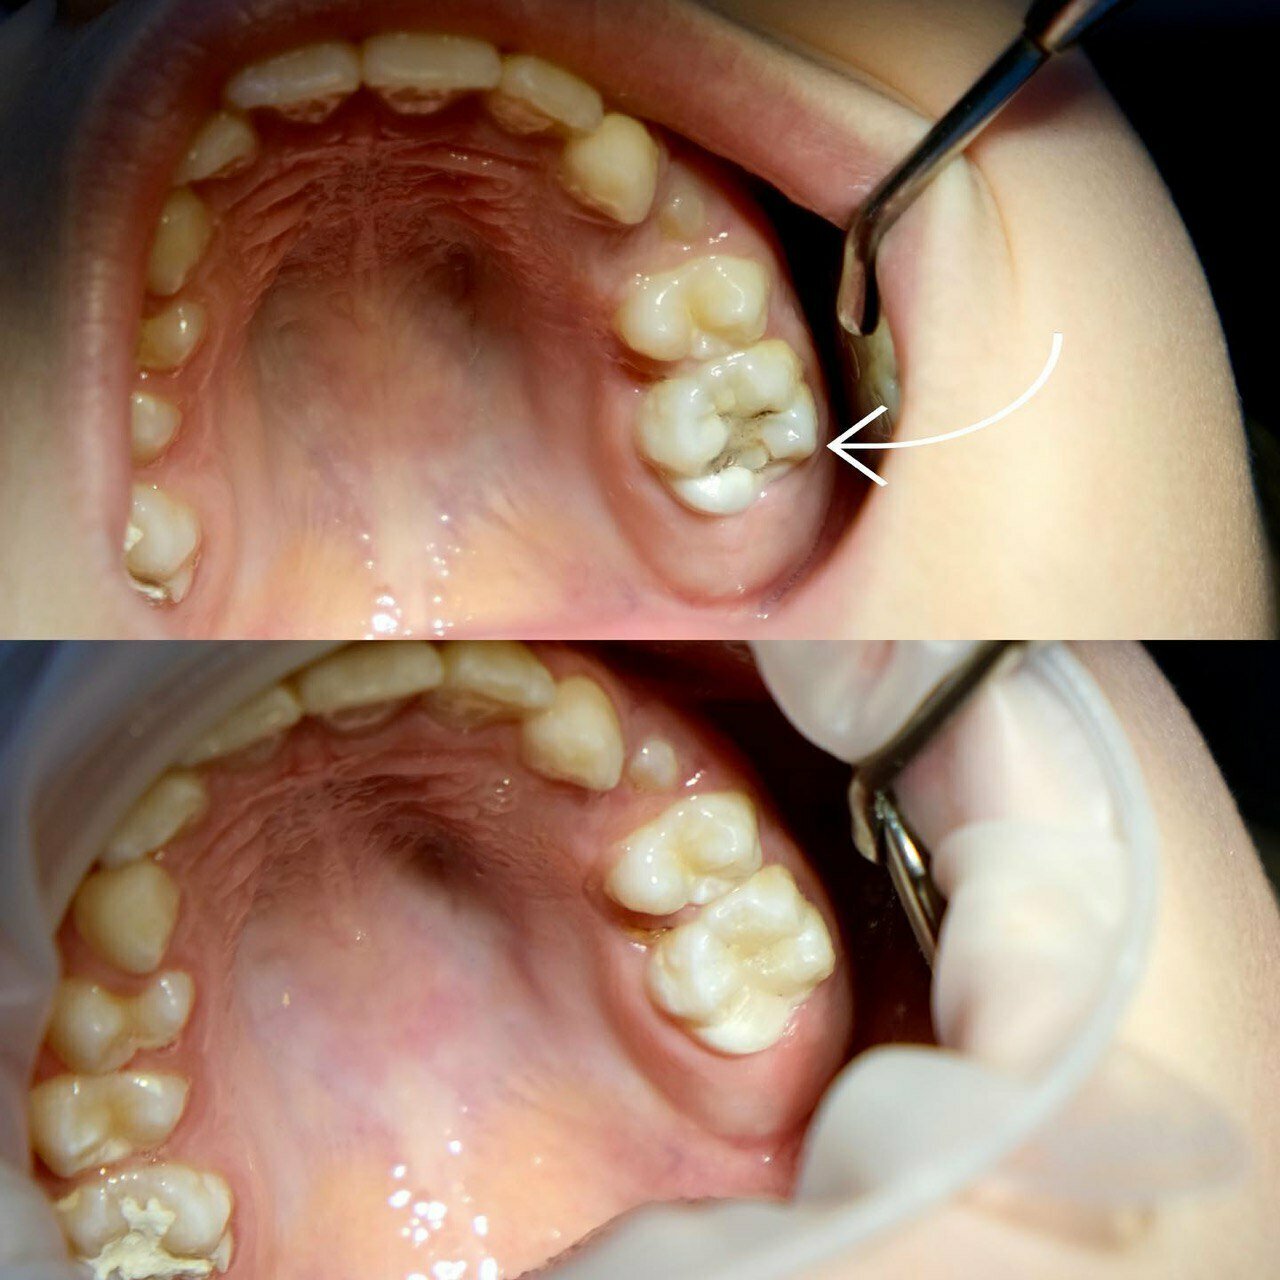

Клиника предоставляет услуги по всем основным направлениям стоматологии, включая общую стоматологию, ортодонтию, хирургическую и эстетическую стоматологию, а также детскую стоматологию. Среди дополнительных услуг: лечение кариеса, пломбирование, удаление зубов, имплантация, протезирование, отбеливание, установка виниров и брекетов, лечение десен и каналов, рентгенография, челюстно-лицевая хирургия и френулопластика.

- лечение кариеса

- Быстрое и профессиональное лечение кариеса.

Вылечили кариес двух зубов быстро и профессионально. Врачи грамотные, оборудование новейшее. Ситуация была достаточно запущенная, но за несколько посещений все сделали. Обошлось без удаления, чему я очень рад. Теперь только сюда буду обращаться.